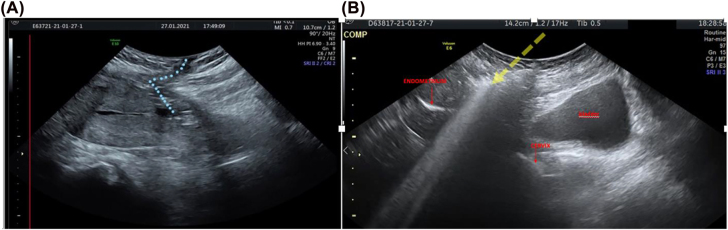

Objectives: The occurrence of a uterocutaneous fistula (UCF) as an uncommon and severe complication of caesarean section (CS). The aim of this study was to describe two cases of UCFs after CS and to discuss about symptoms, diagnosis and treatment.

Case presentation: Both women few days after CS had surgical site infection, fever and elevation of lab inflammation markers. bacterial culture of the wound drainage was positive for Escherichia Coli and Enterococcus Faecalis.

Conclusions: Fistula between uterine and skin is a rare condition but should be considered with signs of inflammation after cesarean section; 2D/3D ultrasound evaluation appears to be useful for diagnosis of UCFs when combined with CT fistulography and MRI in order to obtain early diagnosis and, consequently, a conservative surgery.